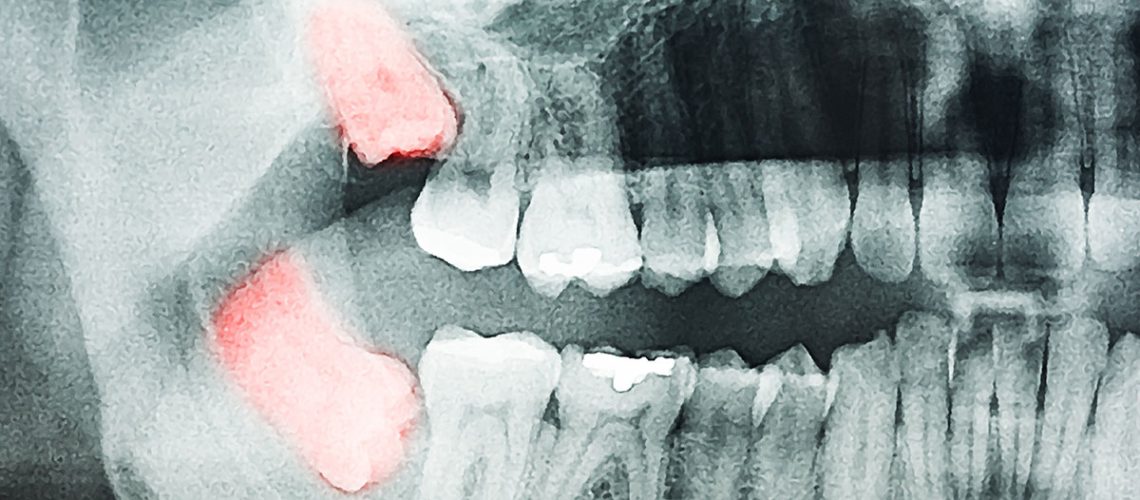

If your dentist sees warning signs during an exam or X-ray, they may recommend early removal to prevent pain or damage.

At Polaris Dental, every extraction starts with a consultation. We’ll take digital X-rays to assess the position of your wisdom teeth and discuss: